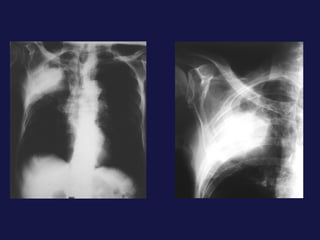

Carcinoma epidermoide ( 30% ). Bronquios centrales, ayuda la citología de esputo. Localización central. Provoca obstrucción bronquial con atelectasia o neumonía postobstructiva sin perdida de volumen mucha cavitación con paredes gruesas e irregulares. 40% lesión periférica,   con bordes espiculados o lobulados. Causa frecuente de pancoast-Tobías.

Extensión local y a distancia. Afectación  hiliar Invasión de la pared torácica (Pancoast). Afectación  pleural ( 8-15%). Afectación mediastínica. Linfangitis carcinomatosa. Metástasis extratorácicas.

Carcinoma epidermoide (30% ). Bronquios centrales, ayuda la citología de esputo. Localización central. Provoca obstrucción bronquial con atelectasia o neumonía postobstructiva sin perdida de volumen mucha cavitación con paredes gruesas e irregulares. 40% lesión periférica, con bordes espiculados o lobulados. Causa frecuente de pancoast-Tobías.

Extensión local ya distancia. Afectación hiliar Invasión de la pared torácica (Pancoast). Afectación pleural ( 8-15%). Afectación mediastínica. Linfangitis carcinomatosa. Metástasis extratorácicas.